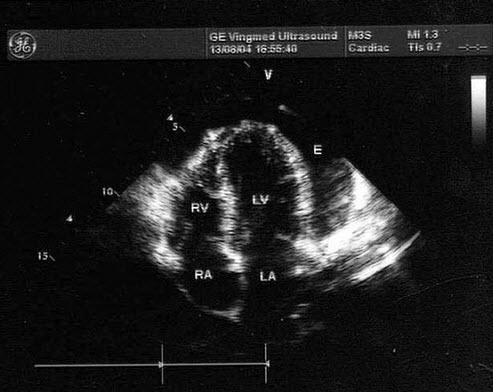

38、单项选择题

该M型图提示()